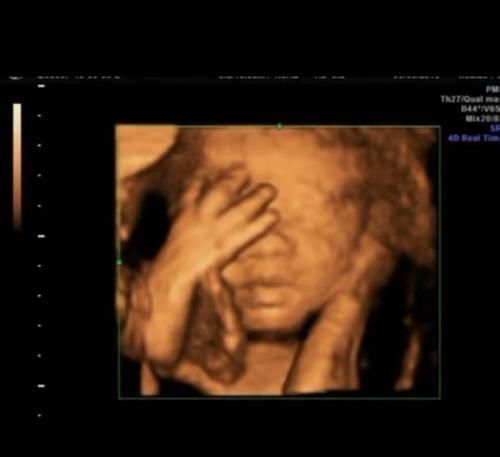

妊娠晚期胎儿的频繁运动也是由于婴儿活动的增加。实际上,这是婴儿发育的信号。频繁的胎儿运动也表明婴儿即将“出来”。

四维检查与其他要求孕妇空腹的检查不同,因此怀孕的母亲在进行四维检查之前应先吃点东西以确保足够的体力,除了饱肚子外,还必须小心不要穿一件衣服以方便检查,缩短不必要的时间并减少患感冒的风险。